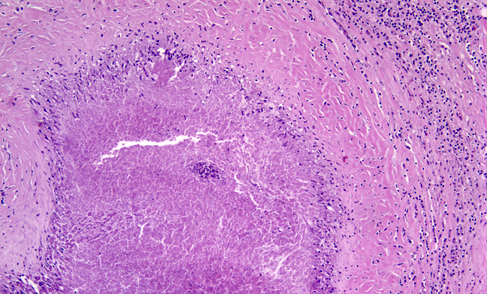

The protozoon Toxoplasma gondii infects approximately one-third of the world’s population. The organism reproduces sexually in the intestinal tract of cats and forms oocysts that are excreted in cats’ feces. Protozoa released form oocysts ingested by animals and humans invade the brain, eye, heart, skeletal muscle, and other organs, where they form tissue cysts. Humans and animals are infected from oocysts in cat feces and from poorly cooked meat containing tissue cysts. Parasites released from oocysts and tissue cysts reside in cell vacuoles and are protected from host defenses. Most primary infections are asymptomatic or cause a self-limited granulomatous lymphadenitis. Latent infections are also silent. If the primary infection occurs during pregnancy, toxoplasma may cross the placenta and cause a devastating necrotizing encephalitis and chorioretinitis in the fetus. The end result of congenital toxoplasmosis is severe brain damage, microcephaly, cerebral calcifications, and blindness. Reactivation of latent toxoplamosis in immunosuppressed individuals, such as patients with HIV/AIDS, causes toxoplasma encephalitis, characterized by necrosis and mononuclear cell infiltrates. The lesions contain single organisms and cysts, which can be identified histologically or by immunohistochemistry. About 25% of patients dying from AIDS have toxoplasma encephalitis.